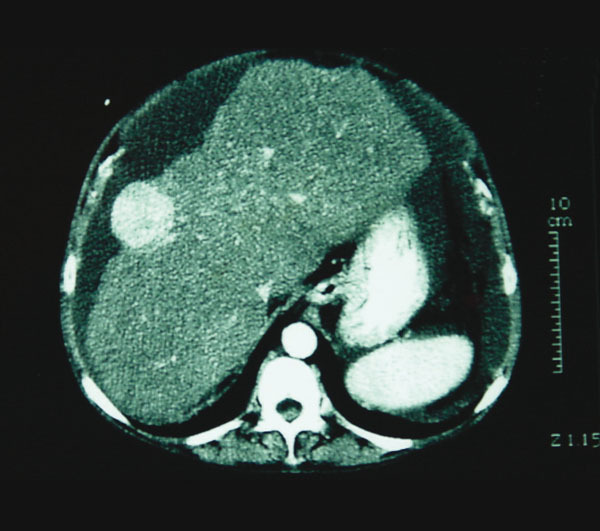

La Revue du Praticien - Jacques Belghiti Lésion hypervascularisée à la phase artérielle, périphérique et sous capsulaire. Présence d’une atrophie hépatique et d’ascite